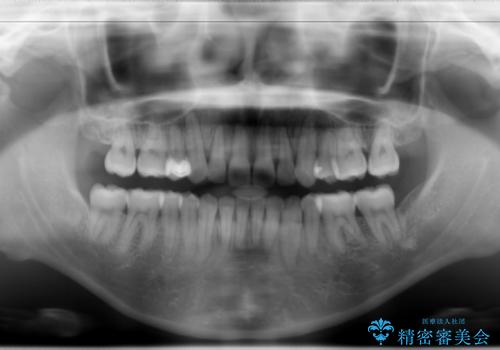

- 上顎両側第1小臼歯、下顎左側第2小臼歯の3本を抜歯、ラビアルのワイヤー矯正を計画した。